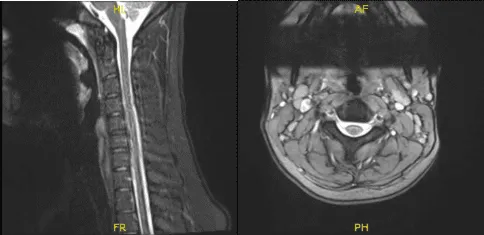

Tras una semana, el paciente regresó con resultados de la resonancia magnética y mostró que la columna cervical mostró un resultado significativo de enderezamiento de la lordosis cervical normal, compatible con un elemento de espasmo muscular, y la resonancia magnética mostró desgarro del labrum glenoides superior que se extendía hacia el ancla, la cabeza larga y el tendón del bíceps.

MRI-3T Columna cervical sin contraste

Artrograma MRI-3T en hombro izquierdo